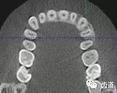

上頜尖牙埋伏阻生在CBCT中的影像